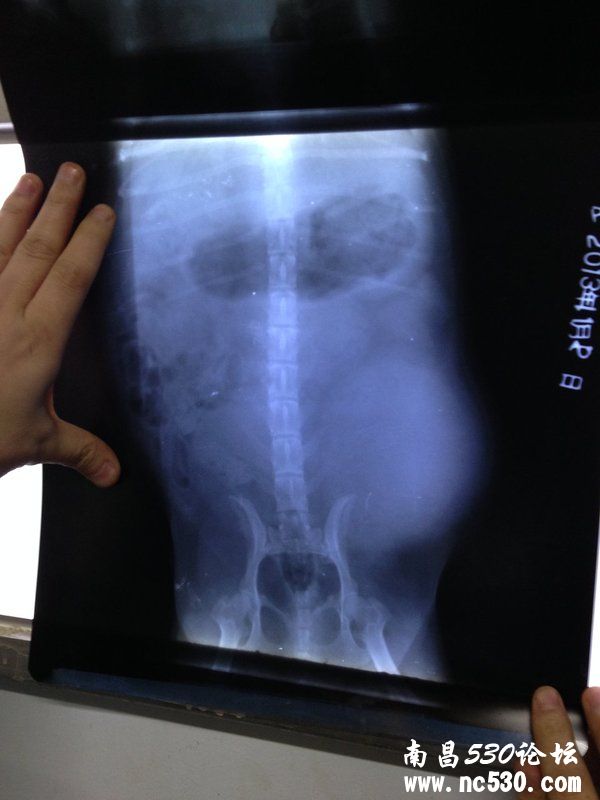

[疾病诊断] 狗恶性肿瘤转移 附X光片

是否绝育或去势:已节育精神状态:不爱动,老趴着。走路缓慢食欲如何:基本正常排便如何:基本正常我家狗一年前做的乳腺肿瘤切除手术和节育,左侧乳腺全部切除,病理结果是恶性肿瘤。医生建议化疗,如果保守治疗医生预计最多活6个月。我们选择了保守治疗,每天服用托消化胶囊。到今天正好已经一年零半个月了。两周前开始狗的精神不好,不爱活动,遛的时候走路也缓慢,不跑。就是在屋里趴着睡觉,吃饭没什么影响,喝水也很多。今天在摸它的时候突然发现后背靠近右后腿位置到右侧腹部肿的很厉害,一只手掌能包住的大小,很硬。立刻去医院检查,照了X光片,医生说是癌细胞转移,怀疑很有可能是髂下淋巴瘤,还说我家狗的情况很特殊,一般都是往肺部内脏等地方转移,而它往下边转移。 根据片子医生说肿瘤已经把膀胱挤一边去了,肿瘤很大。建议手术切除,还说手术的难度很高,首先不确定肿瘤的生长情况,不知道有没有粘连到直肠等地方,而且现在肯定粘连肌肉,切除的面积很大,还需要贴片。 医生说只有开刀后才能知道真正的情况,看是否可以切除,有可能不能切除。 医生还说也有可能是什么血管瘤(不记得名字了),说CT可以查出是不是,如果不是血管就是髂下淋巴瘤。 如果不手术的话那意思基本就是等死了,等到肿瘤再生长压迫直肠什么的。 因为是癌症,再加上手术那么大的风险和难度,我犹豫了。 不知道手术的意义有多大,医生一直在说手术肯定比不手术好。 我从网上查不到任何关于髂下淋巴瘤的资料,希望有人能帮我提供一些有效资料参考或是建议,我家狗这种情况是否还有必要手术。非常感谢!

狗恶性肿瘤转移 附X光片